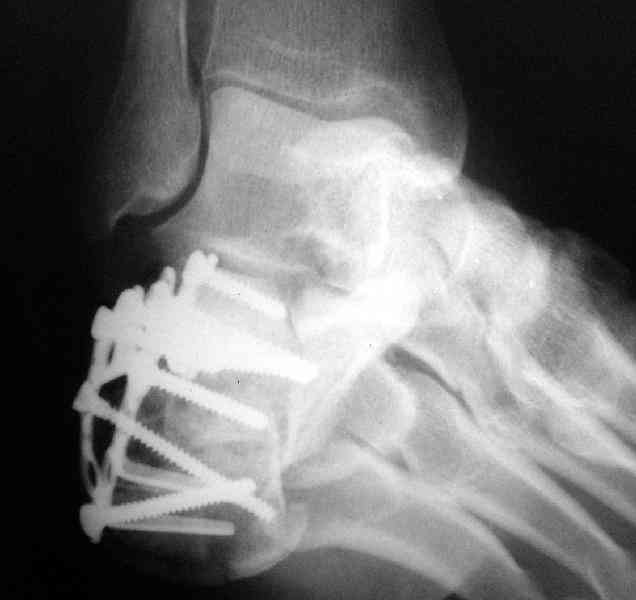

Re: Перелом пяточной кости

Открытый и закрытый способы лечения.